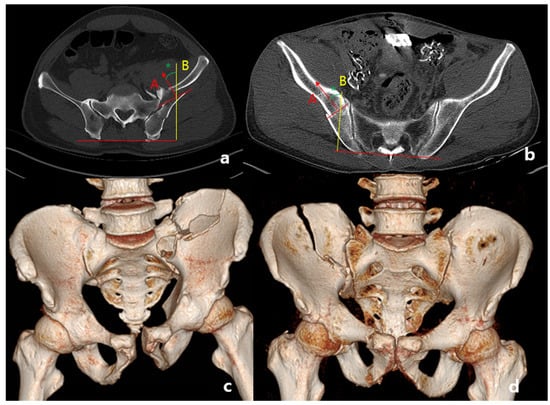

2.1. Classification of Fracture

2.2. Definition of Anterior Sacroiliac Fracture Dislocation

2.3. Radiologic Assessment